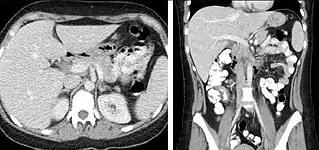

The most common technique is to perform portal venous phase imaging in the abdomen and pelvis (approximately 60–90 seconds after contrast administration, figure 2). This results in near optimal contrast opacification of the majority of the solid abdominal organs and it is used for a wide variety of indications: nonspecific abdominal pain; hernia; infection; masses (with a few exceptions such as hypervascular, renal, and some hepatic tumors); and in most follow-up examinations. As a general rule, this single phase is adequate unless there is a specific clinical indication that has been shown to benefit from other phases.

- FIGURE 2. Contrast enhanced CT demonstrating parenchymal enhancement of the intra-abdominal organs in the portal venous phase (axial left, coronal reformat right).